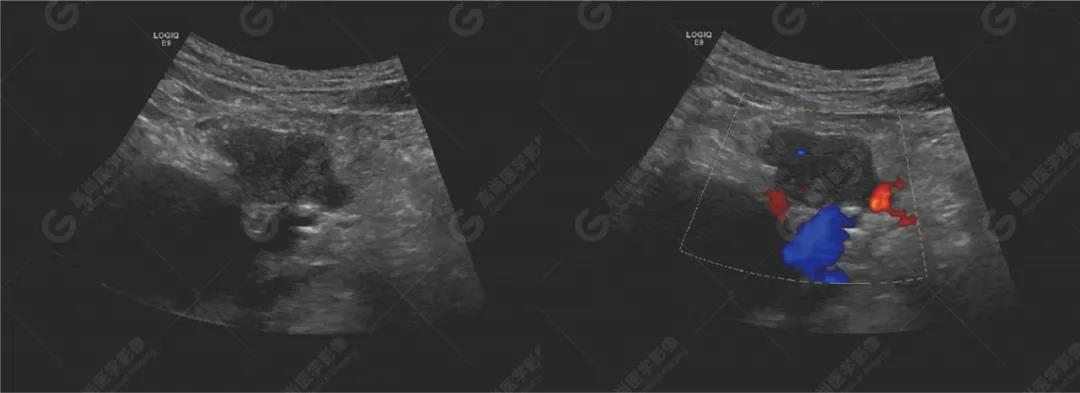

超聲檢查所見(jiàn)胰腺形態(tài)不規(guī)則,胰頭探及兩個(gè)實(shí)性低回聲團(tuán),大小分別約48mm×22mm、30mm×23mm,邊界不清,形態(tài)不規(guī)則,內(nèi)回聲欠均勻,CDFI顯示內(nèi)部可見(jiàn)少許血流信號(hào)。主胰管無(wú)擴(kuò)張。

肝門處探及一大小約66mm×40mm的梭形無(wú)回聲,上方與膽總管相連,下方顯示不清,壁光滑,內(nèi)透聲好,未見(jiàn)明顯異?;芈暎珻DFI顯示內(nèi)未見(jiàn)血流信號(hào)。肝內(nèi)膽管左支稍擴(kuò)張,呈平行管征。

腹膜后可見(jiàn)數(shù)個(gè)低回聲,較大約25mm×13mm,邊界清,形態(tài)不規(guī)則,部分相互融合,CDFI顯示其內(nèi)可見(jiàn)點(diǎn)狀血流信號(hào)。

提示胰腺實(shí)性占位性病變(考慮胰腺癌)

腹膜后淋巴結(jié)腫大(考慮轉(zhuǎn)移性)

肝門囊性占位(先天性膽總管囊腫?)

肝內(nèi)膽管局部稍擴(kuò)張